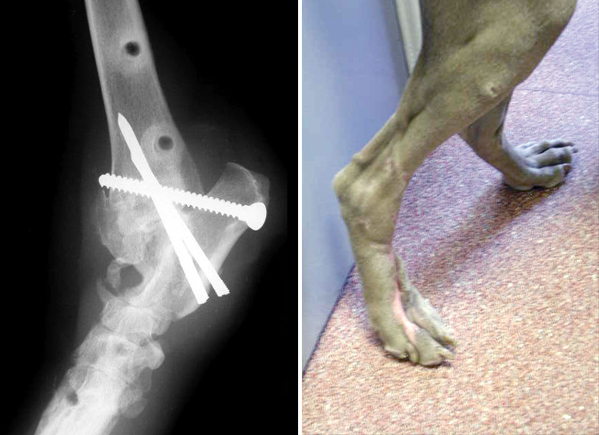

Case 5

This Weimaraner was hit by a car and sustained multiple fractures of the tarsal joint (the ankle) in addition to severe skin injuries. In two operations the joint was fused using multiple pins that penetrated the skin and were attached to connecting bars on the outside and inside of the limb (an external skeletal fixator).

X-ray and photograph of the same Weimeraner one year after the injury, showing the fused tarsal joint (arrow) with remaining metal implants and residual scars on the paw.